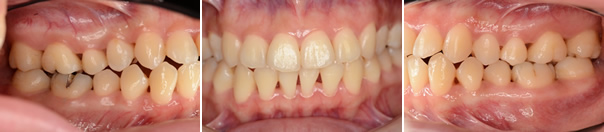

■28歳女性

仕事が忙しく、かなり疲れています。数日前に風をひき、朝起きたら、何もしなくても歯肉がズキズキ痛み、歯ブラシの毛先がちょっと触れただけで飛び上がるほど痛む

抗菌剤(メトロニタゾール)の投与とクロルヘキシジン溶液の洗口をおこない免疫力をあげて、栄養状態を改善し、十分な休息を取るるようご指導しました。症状が軽減した後、通常の基本治療を行いました。

・メインテナンス時